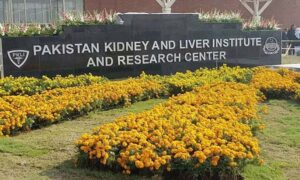

پاکستان میں پہلی بار ایک جگر کی دو مریضوں میں پیوند کاری اور لبلبہ ٹرانسپلانٹ کا کامیاب تجربہ

راولپنڈی کے برین ڈیڈ مریض کے اعضاء سے 7 افراد کی جان بچائی گئی